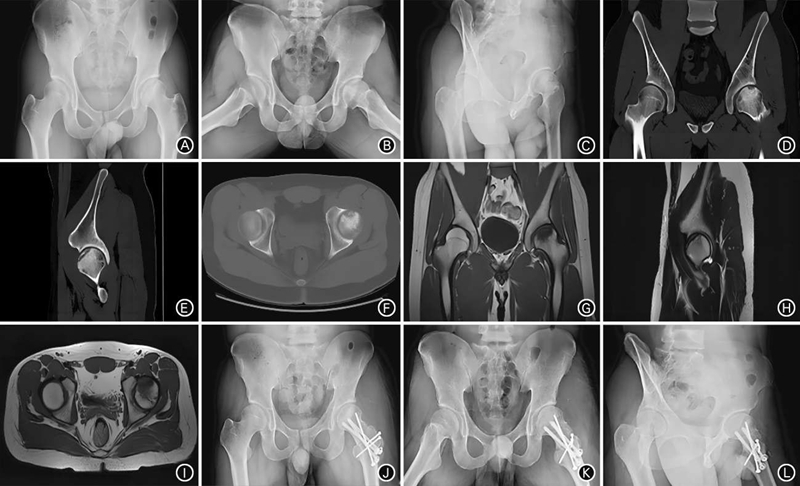

图2 患者男,22岁,训练伤致左髋疼痛1年入院,诊断为SIFFH,行保留圆韧带的股骨颈旋转截骨术。A、B.术前双髋关节正位、蛙式位X线片示左侧股骨头负重区密度降低,软骨下明显骨折;C~D.术前左髋关节65°斜位X线片示髋关节前侧覆盖良好;D~F.术前双髋关节冠状位、矢状位及水平位CT示骨折累及股骨头前1/3;G~I.术前双髋关节冠状位、左侧单髋关节矢状位、双髋关节水平位MRI T1加权像示股骨头骨折累及股骨头前1/3;J、K.术后1年双髋关节正位、蛙式位X线片示股骨颈及大转子处截骨后愈合良好,内固定物位置良好;L.术后1年左髋关节65°斜位X线片示股骨头覆盖良好。注:SIFFH为股骨头软骨下骨折